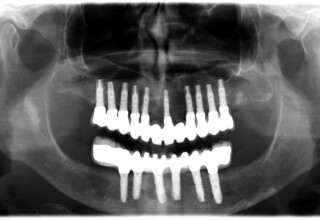

Ολική Στοματική Αποκατάσταση σε Εμφυτεύματα με διαφορετική προσέγγιση στην Άνω και Κάτω Γνάθο

Κάτω γνάθος: εξαγωγές, άμεση τοποθέτηση εμφυτευμάτων και άμεση φόρτιση(την ίδια ημέρα) με προσωρινή γέφυρα

Άνω γνάθος: σταδιακές εξαγωγές, σταδιακή τοποθέτηση εμφυτευμάτων και σταδιακή ενσωμάτωση τους στην προσωρινή γέφυρα ώστε η ασθενής να μην μείνει ούτε μια ημέρα χωρίς αποκατάσταση. Στόχος η συνεχής λειτουργική και αισθητική αποκατάσταση της ασθενούς χωρίς άμεση φόρτιση των εμφυτευμάτων λόγω ανατομικών ιδιαιτεροτήτων.

Χρησιμοποιήθηκαν παλαιές χαμογελαστές φωτογραφίες της ασθενούς γιατί είχε χαθεί τελείως το φυσικό σχήμα των δοντιών εξαιτίας των πολλαπλών προσθετικών προσπαθειών που είχαν γίνει στο παρελθόν. Μεταφέρθηκε στην προσωρινή γέφυρα η σχέση των φυσικών δοντιών μεταξύ τους άλλα και με τα χείλη. Δοκιμάστηκε η φώνηση και η μάσηση με δυο διαφορετικές προσωρινές άνω γέφυρες και εκτιμήθηκε η αισθητική απόδοση τους. Αφού επιτεύχθηκαν σε βαθμό ικανοποιητικό η φώνηση και η αισθητική εμφάνιση της οδοντοφυΐας, η προσωρινή αποκατάσταση χρησιμοποιήθηκε ως οδηγός για την τελική.

Αρχικό

Ενδιάμεσο

Τελικό